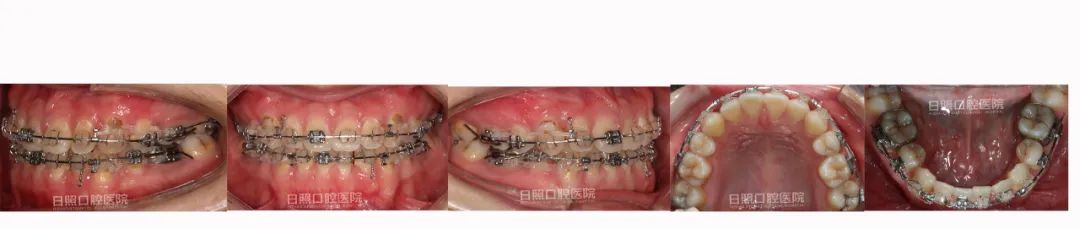

双侧磨牙近中关系,上下前牙地包天,可退至前牙对刃,23、25龋坏,14残根,上下中线不齐。两侧面部不对称,脸型为凹面型。

治疗中口内照

治疗后口内照